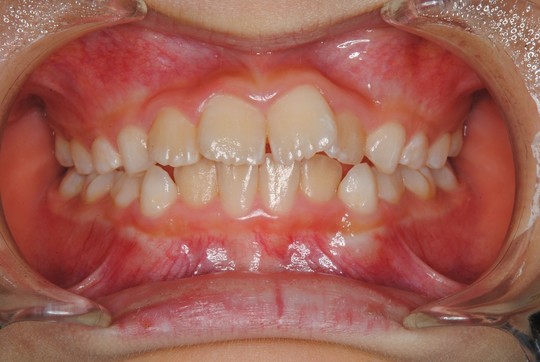

治療前

治療開始年齢 10才

上下の歯並びが悪いので直して欲しいとのことで来院されました。